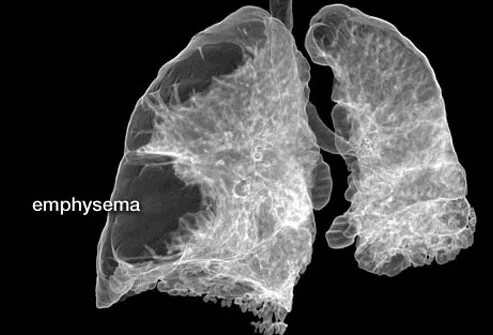

慢性阻塞性肺病:肺氣腫

肺氣腫是一種肺部疾病。在肺氣腫中,肺泡(肺中促進二氧化碳和氧氣交換的小氣囊)受損并死亡。二氧化碳和氧氣沒有交換,最終肺泡死亡,在肺部留下空洞,導致肺組織丟失和 COPD 癥狀加重。肺氣腫的癥狀通常包括呼吸急促,有時還包括咳嗽和喘息。肺氣腫的治療可能包括支氣管擴張藥物、類固醇、抗生素和氧氣。強烈建議戒煙。

通常,肺大皰切除術適用于與肺氣腫相關的慢性阻塞性肺病患者。當氣囊壁被破壞時,會形成更大的氣腔(大皰)。大皰切除術將去除大皰并允許一些肺擴張。

肺容積減少

肺減容手術 (LVRS) 發生在患有與肺氣腫相關的COPD的患者身上。該程序通過去除受損組織來縮小肺部大小。剩余的肺和周圍的肌肉能夠更有效地工作,并允許功能性氣道進行更好的氣體交換。